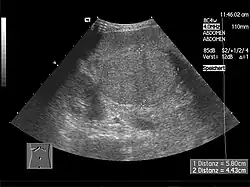

Im Ultraschall stellt sich die Leber inhomogen dar. Der Leberrand ist wellig, die Binnengefäße sind rarefiziert. Der Lobus caudatus kann vergrößert sein. Sehr gut können mit dem Ultraschall ein Aszites und eine Milzvergrößerung (Splenomegalie) erkannt werden. Eine verbesserte Form der Sonographie stellt der sogenannte Fibroscan, auch bekannt als transiente Elastografie, dar. Hiermit kann die Fibrosierung, also der Bindegewebsumbau, der Leber ermittelt werden, was ein sehr zuverlässiges Ergebnis zur Diagnosestellung liefert und zukünftig die Leberbiopsie (s. u.) ersetzen könnte. Mit der farbkodierten Doppler-Sonografie lassen sich in der Pfortader ein verminderter Fluss sowie in der Leberarterie ein erhöhter peripherer Widerstand messen.